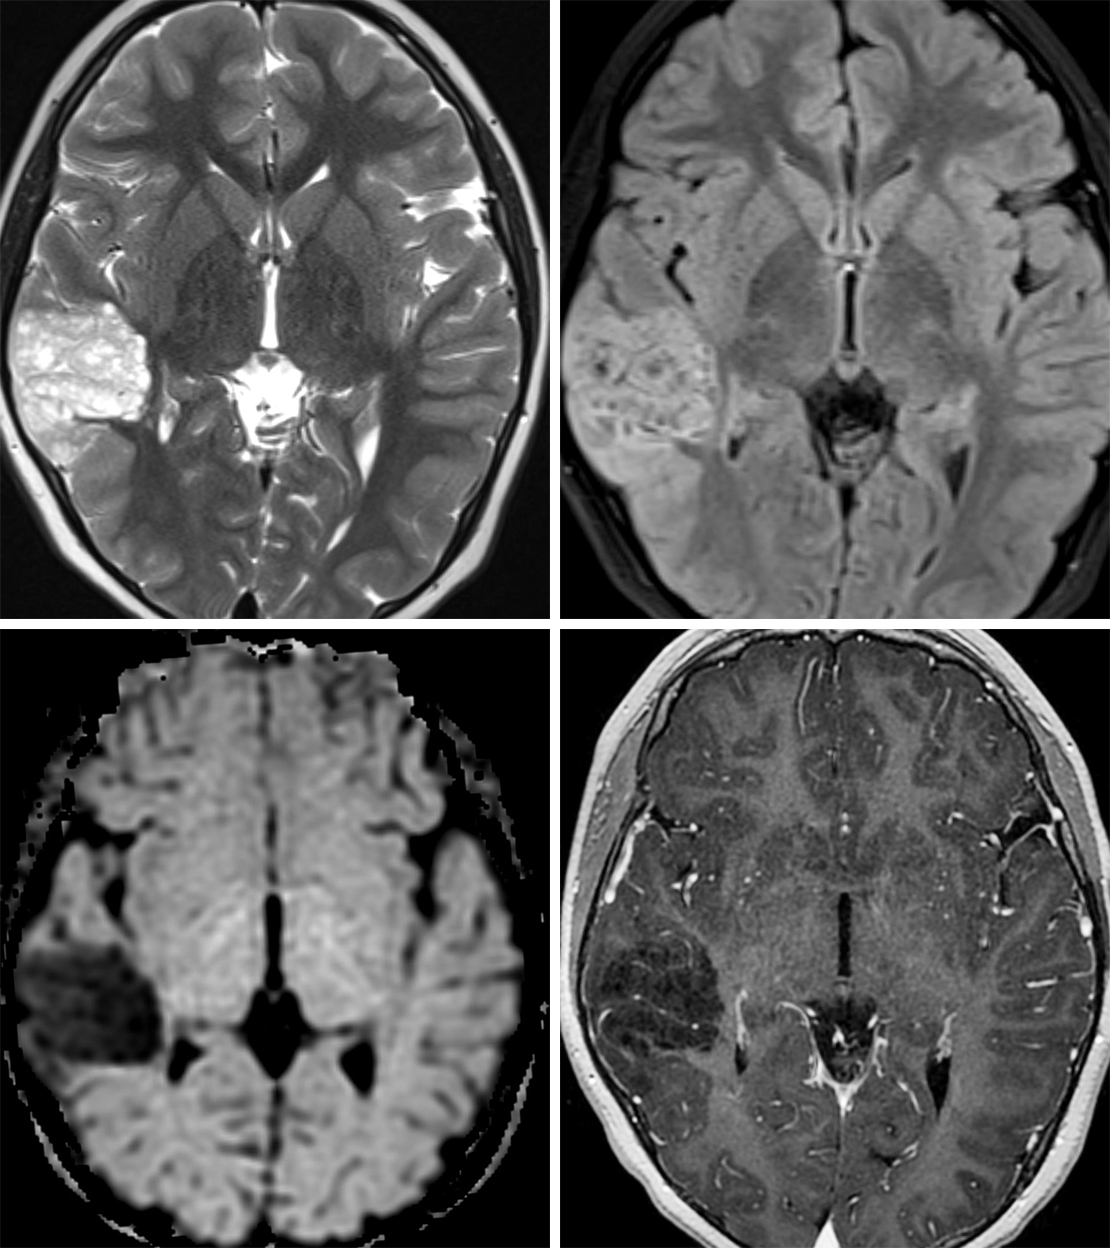

МРТ головного мозга: показания и результаты

Раздел: Визуальный дайджест